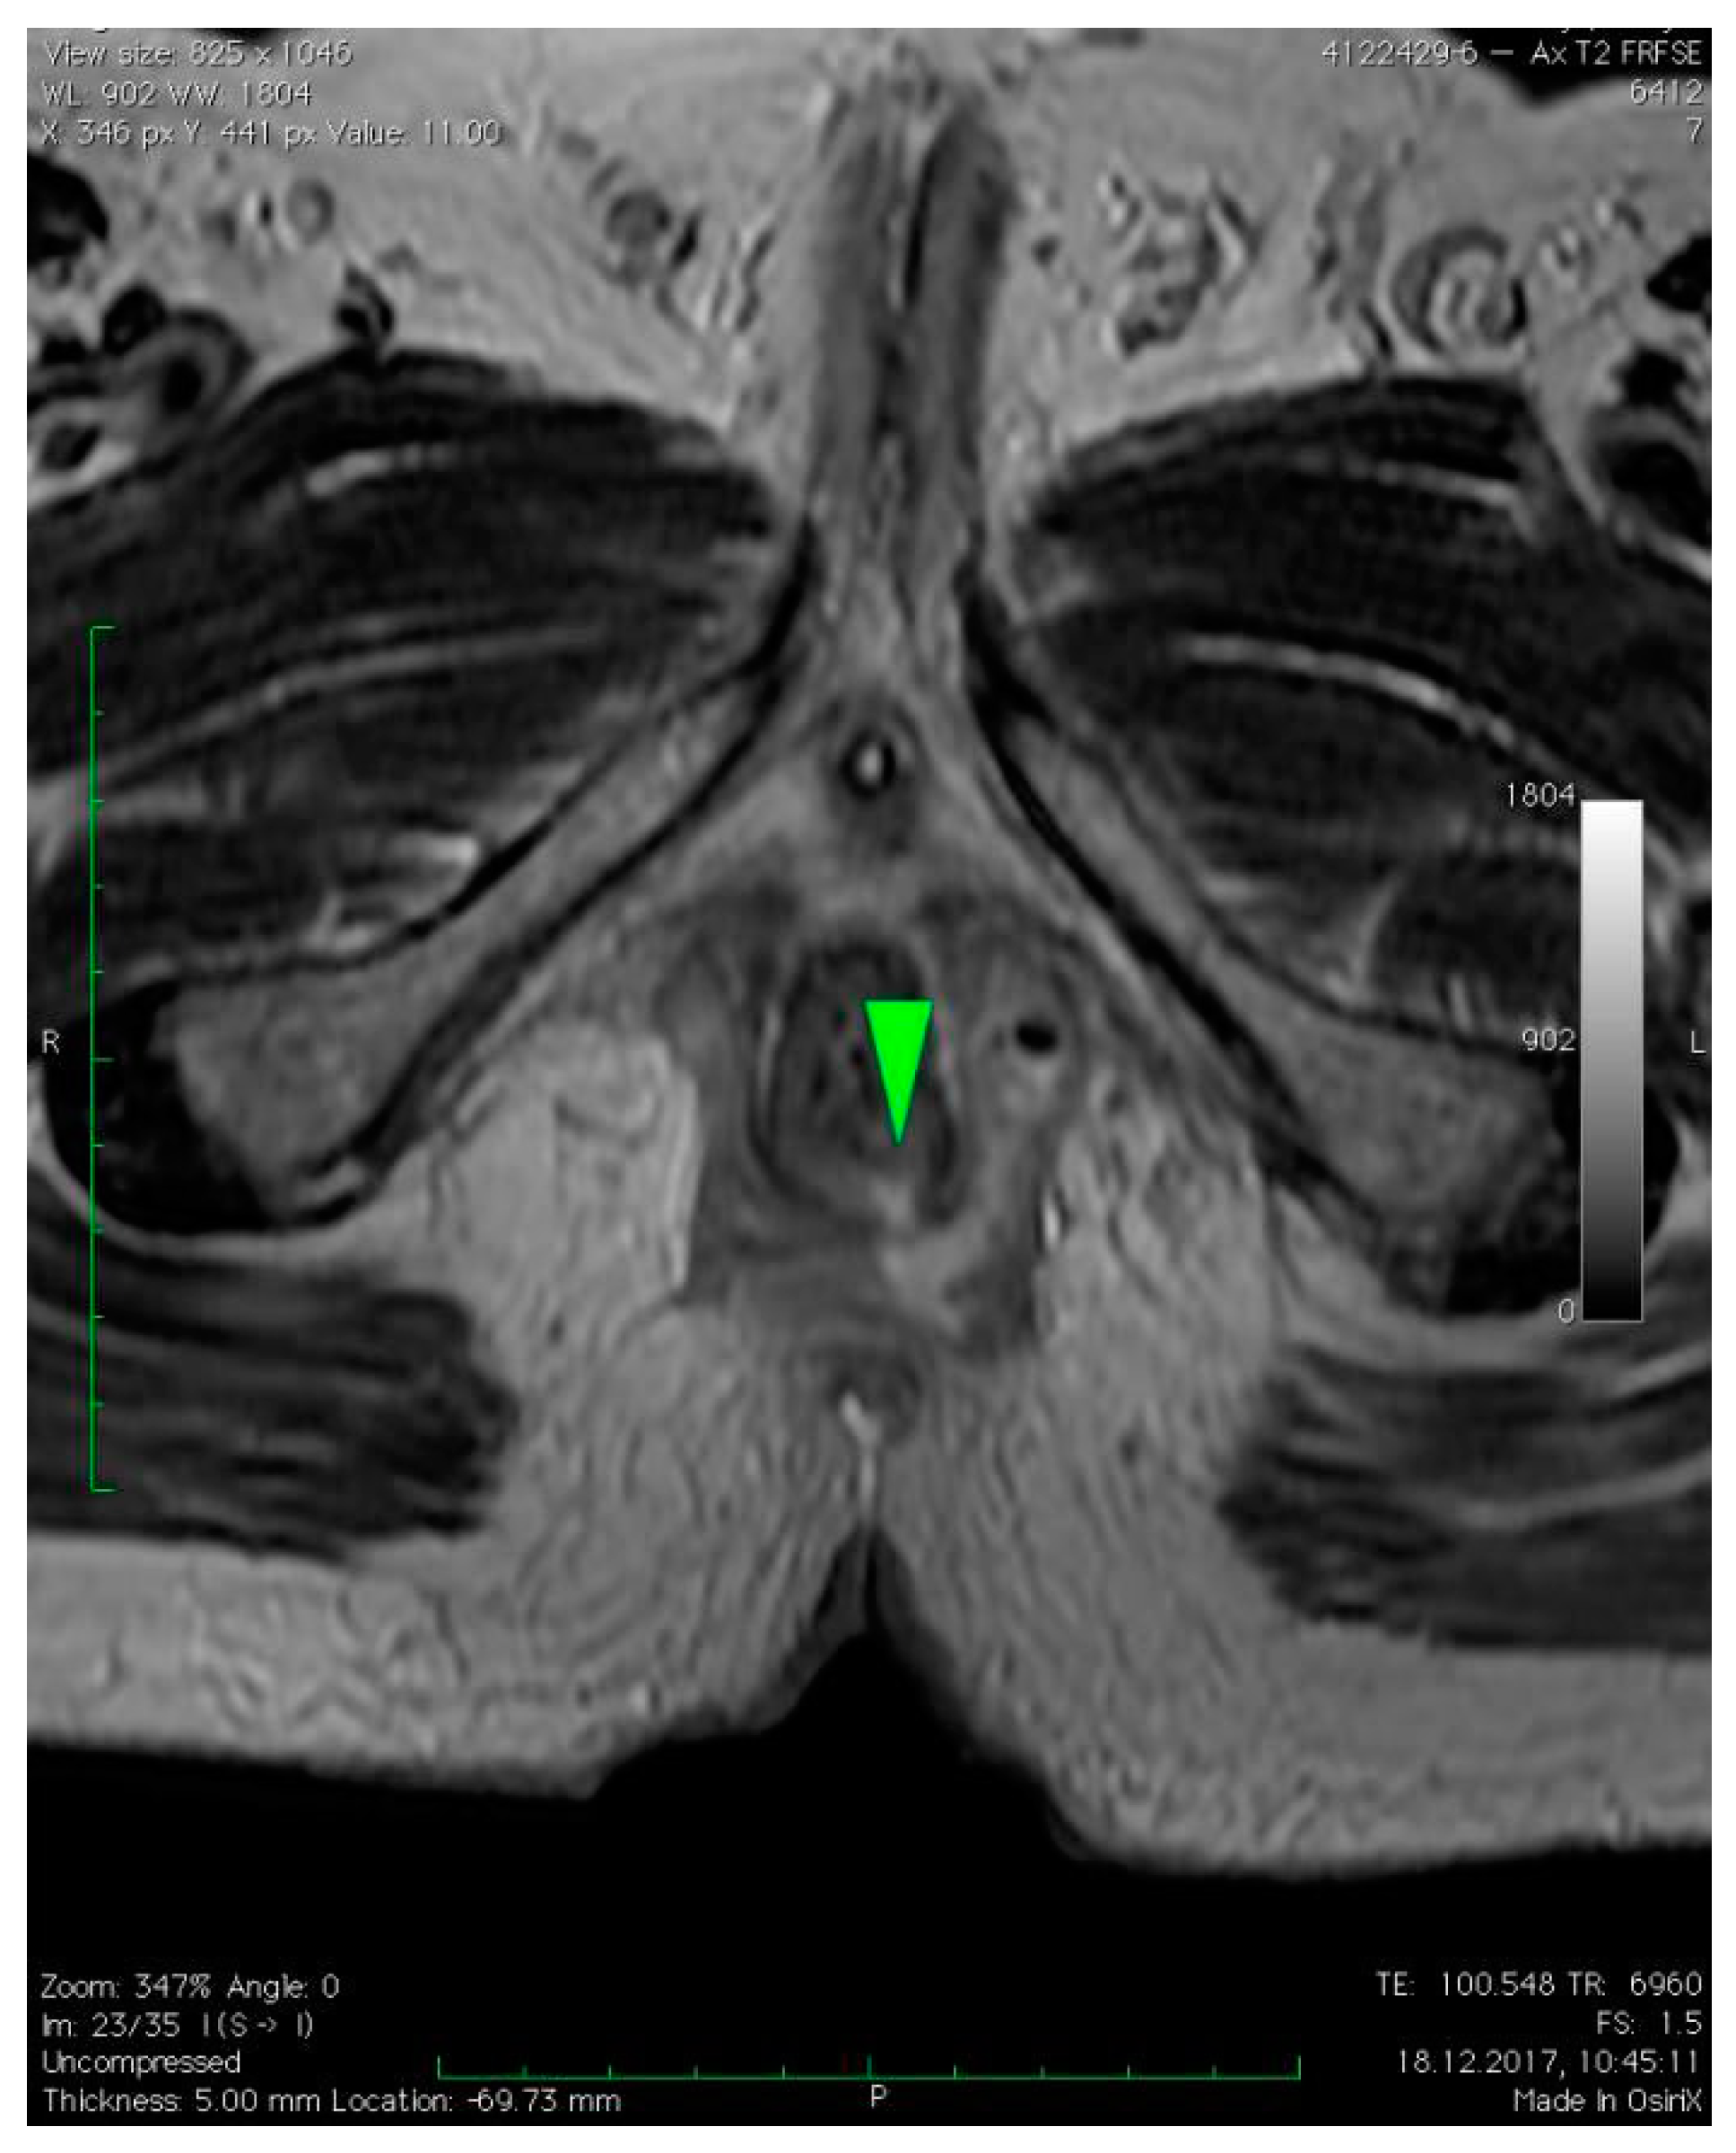

3. Case Presentation